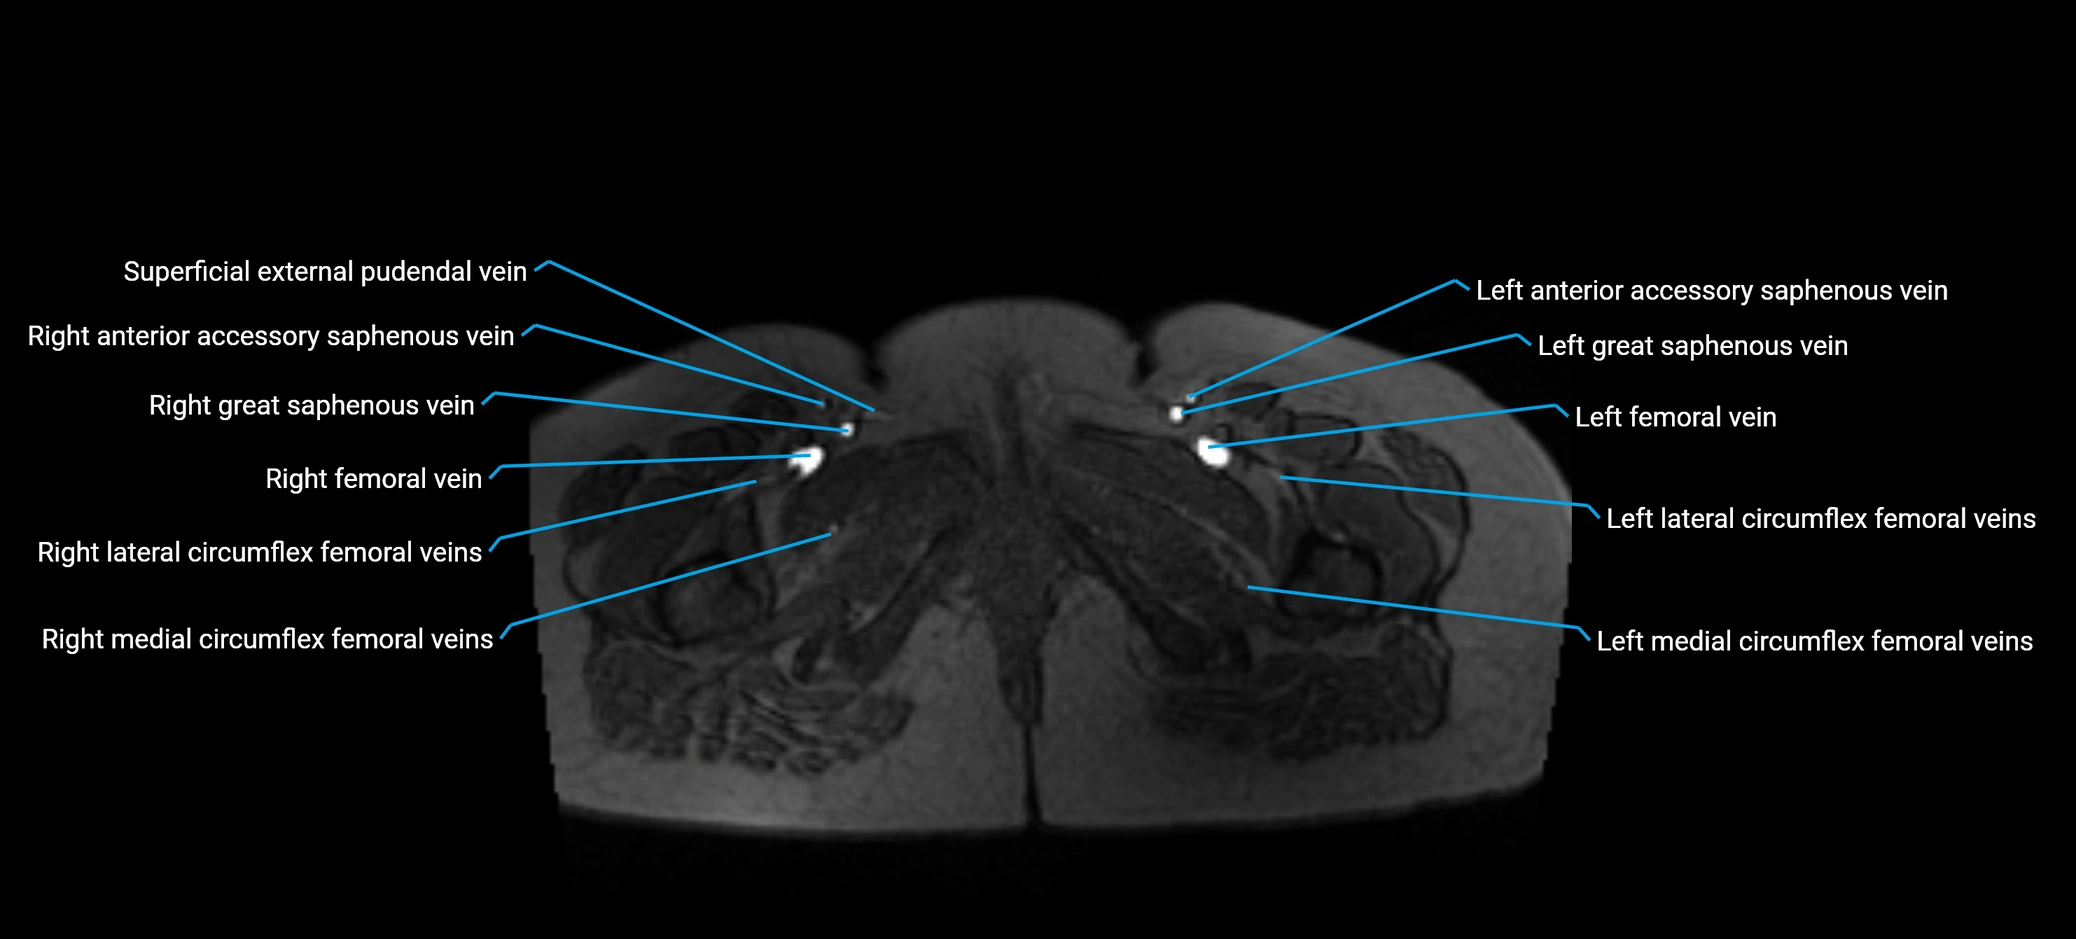

MRI image

image